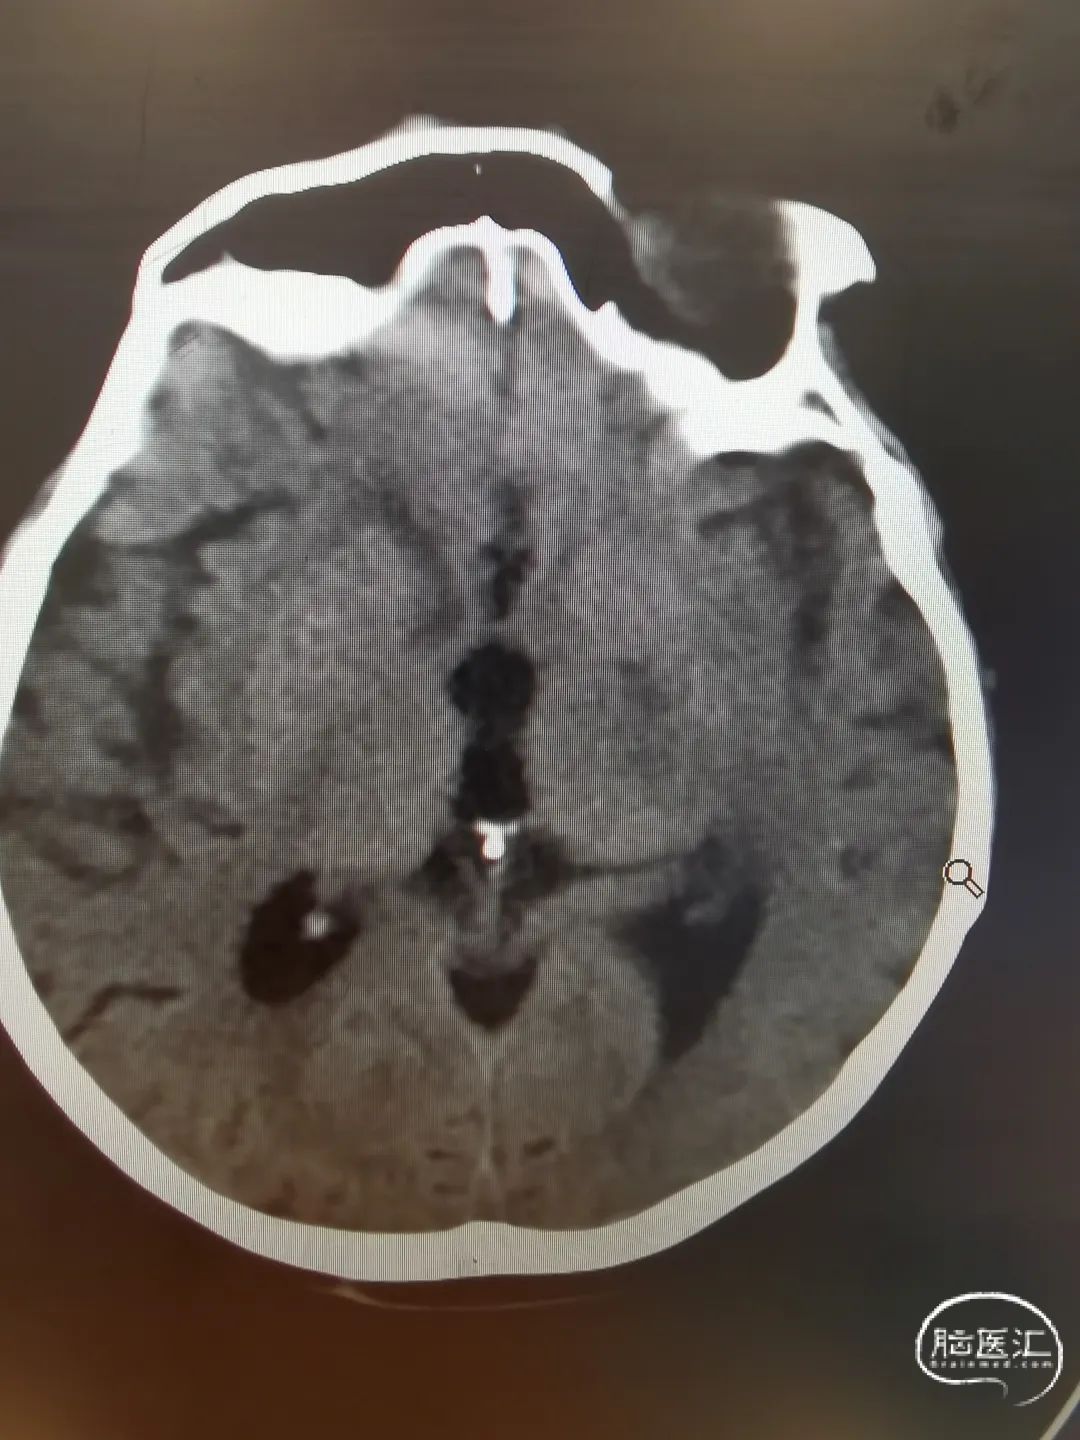

头颅CT未见明显蛛网膜下腔出血。

头颅CTA提示左侧颈内动脉迂曲,双侧血管无闭塞,大脑中动脉M1段起始处动脉瘤。

DSA造影提示主动脉III型弓,左侧颈内动脉迂曲明显,远端血管通畅。

1.左侧大脑中动脉M1段起始处动脉瘤;

2.左侧动眼神经麻痹;